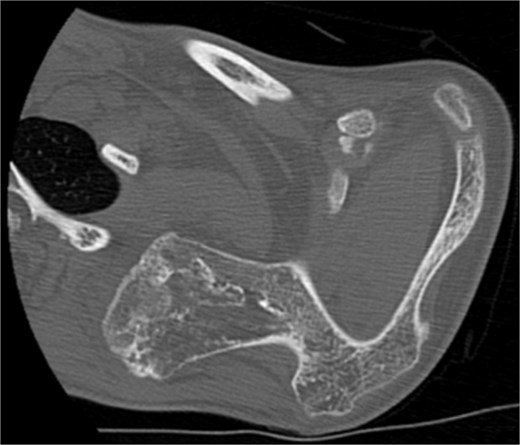

The imaging investigation was initiated by our department, as we were clinically suspicious of the presence of osteochondromas, due to the history of HME in both patients. Both patients were subscribed an anteroposterior X-ray of left shoulder and a CT scan for pre-operative planning. Also, radiographic evaluation of both knees and left forearm were taken and revealed multiple exostoses as a part of the HME follow-up that both girls underwent. The CT scan of the 14 year old patient demonstrated three bony lesions arising from the ventral aspect of left scapula. The largest one extruded from superior angle heading medially to the vertebral bodies. The other two smaller arose one from the lateral angle and one from the inferior angle. The CT scan of the 9 year old patient revealed one bony lesion arising ventrally from the superior angle of the left scapula heading medially as well (Figs 2 and 3). The diagnosis of VSO was made in both cases.

CT of the 14-year-old patient showing the largest lesion arising ventrally from the superior angle of left scapula in axial plane.